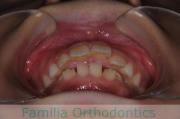

下の前歯が後ろにあるのが気になるとのことで来院されました。非抜歯で行うことも可能でしたが、上下左右から小臼歯抜歯をして治療を行うことをご希望になりました。

マルチブラケット法にて治療を行い、約3年、40回の通院が要でした。

かみ合わせが深い(上の前歯で下の前歯が覆われてしまう)ので、保定をしっかりしないと、また深くなってきてしまいやすいです。